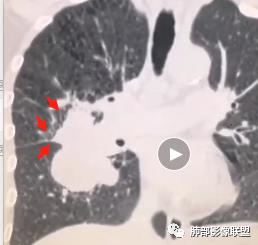

周围小毛刺

小叶间隔增厚?

@吴婧南京市第一医院?吴老师 上叶部分有毛刺,中叶下叶部分有没有毛刺

@南边?潘老师 上叶部分,分叶,毛刺及癌淋怎么解析